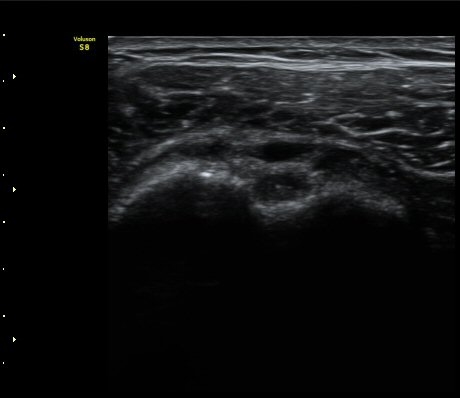

3°³¿ù ÈÄ ÃßÀû°Ë»ç

2049205267_d4912430_US181205109.jpg